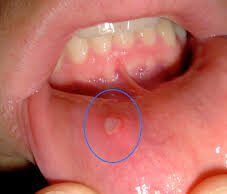

ಬಾಯಿ ಹುಣ್ಣು

1. ಕೊತ್ತಂಬರಿ ಬೀಜದ ಪುಡಿಯನ್ನು ಜೇನುತುಪ್ಪದಲ್ಲಿ ಕಲಸಿ, ನಾಲಿಗೆಯ ಮೇಲೆ ಹಚ್ಚಿಕೊಂಡು ಚಪಡಿಸುತ್ತಿದ್ದರೆ ಬಾಯಿ ಹುಣ್ಣು ಗುಣ ಆಗುವುದು.

2. ಕೊತ್ತಂಬರಿ ಸೊಪ್ಪನ್ನು ಹಸಿಯಾಗಿಯೇ ಹಲ್ಲುಗಳಿಂದ ಜಗಿಯುತ್ತಿದ್ದರೆ ಬಾಯಿಯ ದುರ್ಗಂಧ ಕಡಿಮೆ ಆಗುತ್ತದೆ.

3. ದಿನಕ್ಕೆ...